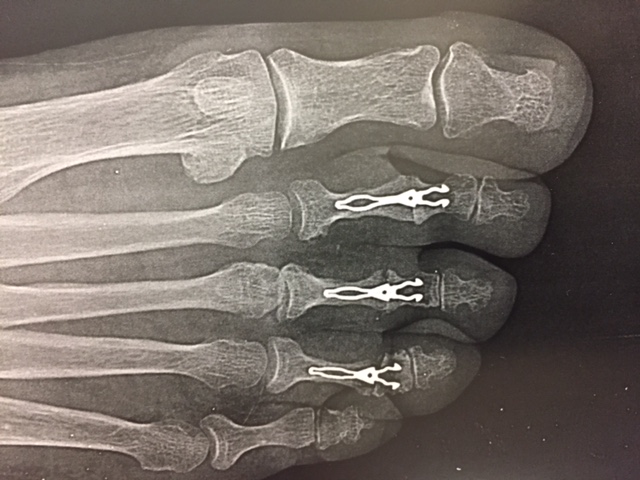

- l’arthrodèse: elle bloque l’articulation en bonne position avec une broche, des vis ou des implants (métalliques ou non).

Arthrodèse interphalangienne proximale avec implants métalliques pour correction d’orteil en griffe